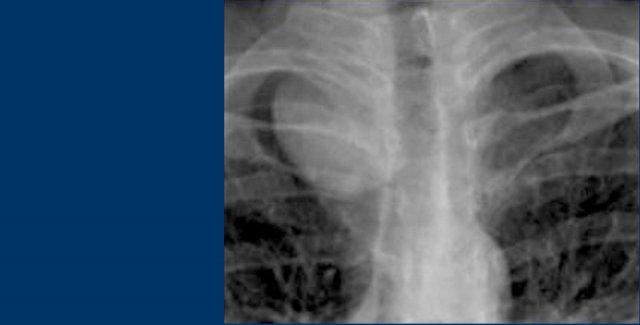

Hãy mô tả các hình ảnh bên trái.

Sau đó tiếp tục.

Trên phim thẳng (PA), có hình ảnh giãn rộng dạng múi của trung thất trên.

Trên phim nghiêng ngực, khoang sáng sau xương ức bị xóa mờ.

Đây là trường hợp bệnh nhân mắc u lympho.

Bên trái là hình ảnh FDG-PET của cùng bệnh nhân.

Có nhiều khối hạch bạch huyết ở trung thất trước, trung thất giữa và thậm chí trung thất sau, lan lên vùng cổ.